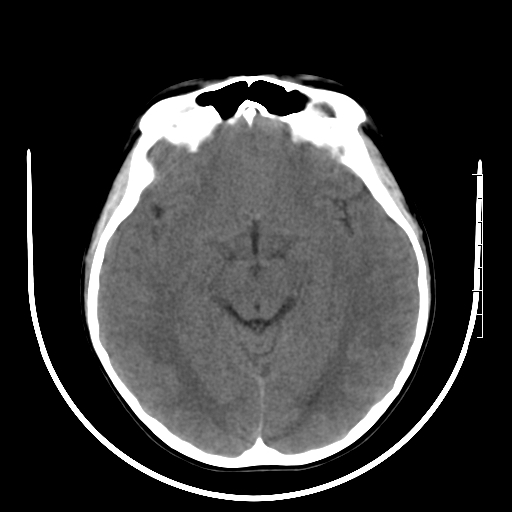

标题: PED3377:m、9y,恶心、呕吐,每月发作2-3次。 [打印本页]

标题: PED3377:m、9y,恶心、呕吐,每月发作2-3次。

颅脑ct轴位平扫颅内未见明确异常。

右侧基底节区见钙化灶

右侧壳核多枚点状钙化灶。去请结合临床。

桥前池是不是有点大?